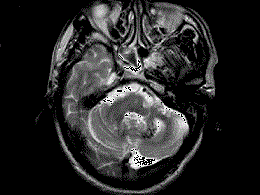

问题 男,49岁,反复发作性癫痫,双手震颤5年,伴头昏行走不稳,生化检查:血清钙降低,血清磷升高,请根据所提供图像,选择最可能的诊断 ( )

选项 A、肝豆状核变性 B、甲旁低 C、一氧化碳中毒性脑病 D、霉变甘蔗中毒 E、Fahr病

答案 B